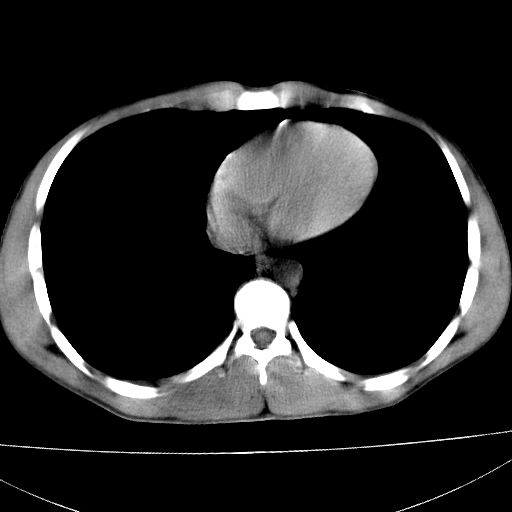

标题: CT15860:男,21岁,腹部外伤2小时伴胸疼。 [打印本页]

标题: CT15860:男,21岁,腹部外伤2小时伴胸疼。

1)肝破裂伴腹腔积液(血)。2)右肾破裂伴右肾包膜下及肾周血肿。3)腹部空腔脏器穿孔可能。4)右侧少量胸腔积液(血)。

1)肝破裂伴腹腔积液(血)。2)右肾破裂伴右肾包膜下及肾周血肿。3)右侧少量胸腔积液(血)。

1)肝破裂伴腹腔积液(血)。2)右肾破裂伴右肾包膜下及肾周血肿。3右侧少量胸腔积液(血)。